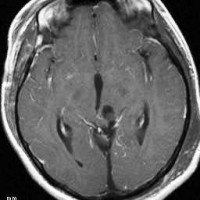

2008年の中脳毛様細胞性星細胞腫の手術ビデオ

左は術前,右は手術直後のMRIです。このビデオを見て,およその手技の順番のみ把握して下さい。